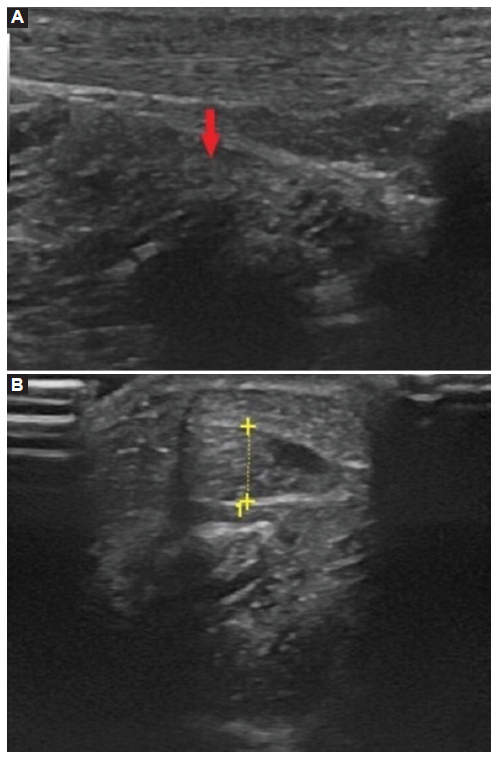

Por ecografía, en el plano longitudinal (Fig. 2A) y transversal (Fig. 2B), se identificó como hallazgo positivo, imagen de ecogenicidad similar al músculo, ocupando el espacio correspondiente a la grasa retrotibial izquierda, preaquileana.

La ecografía muestra imagen hipoecoica, de similar ecogenicidad al músculo, bien delimitada, mientras que en la tomografía computada (TC) aparece como una masa de partes blandas con valores de atenuación equivalentes al músculo, ausencia de calcificaciones en su interior, de localización anteromedial al tendón de Aquiles.